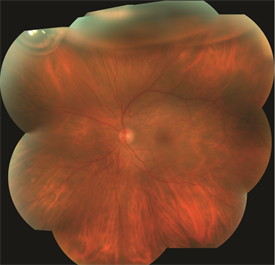

Superior macula-involving retinal detachment with a retinal tear identified with arrow |

Same patient one day after treatment. The retina is reattached and a gas bubble is visible at the top of the eye. |